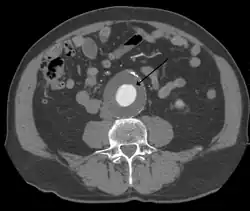

The diagnosis of an abdominal aortic aneurysm can be confirmed by the use of ultrasound. Rupture may be indicated by the presence of free fluid in the abdomen. A contrast-enhanced abdominal CT scan is the best test to diagnose an AAA and guide treatment options.[14]